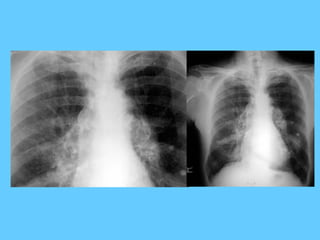

Chronic tuberculosis

Tuberculosis